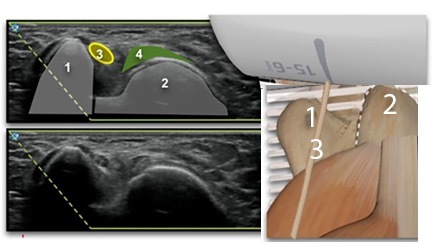

Elbow Cubital Tunnel Injection Transducer Position Graphic and Image

1. Medial Epicondyle

2. Olecranon Process

3. Ulnar Nerve

4. Medial Head of the Triceps